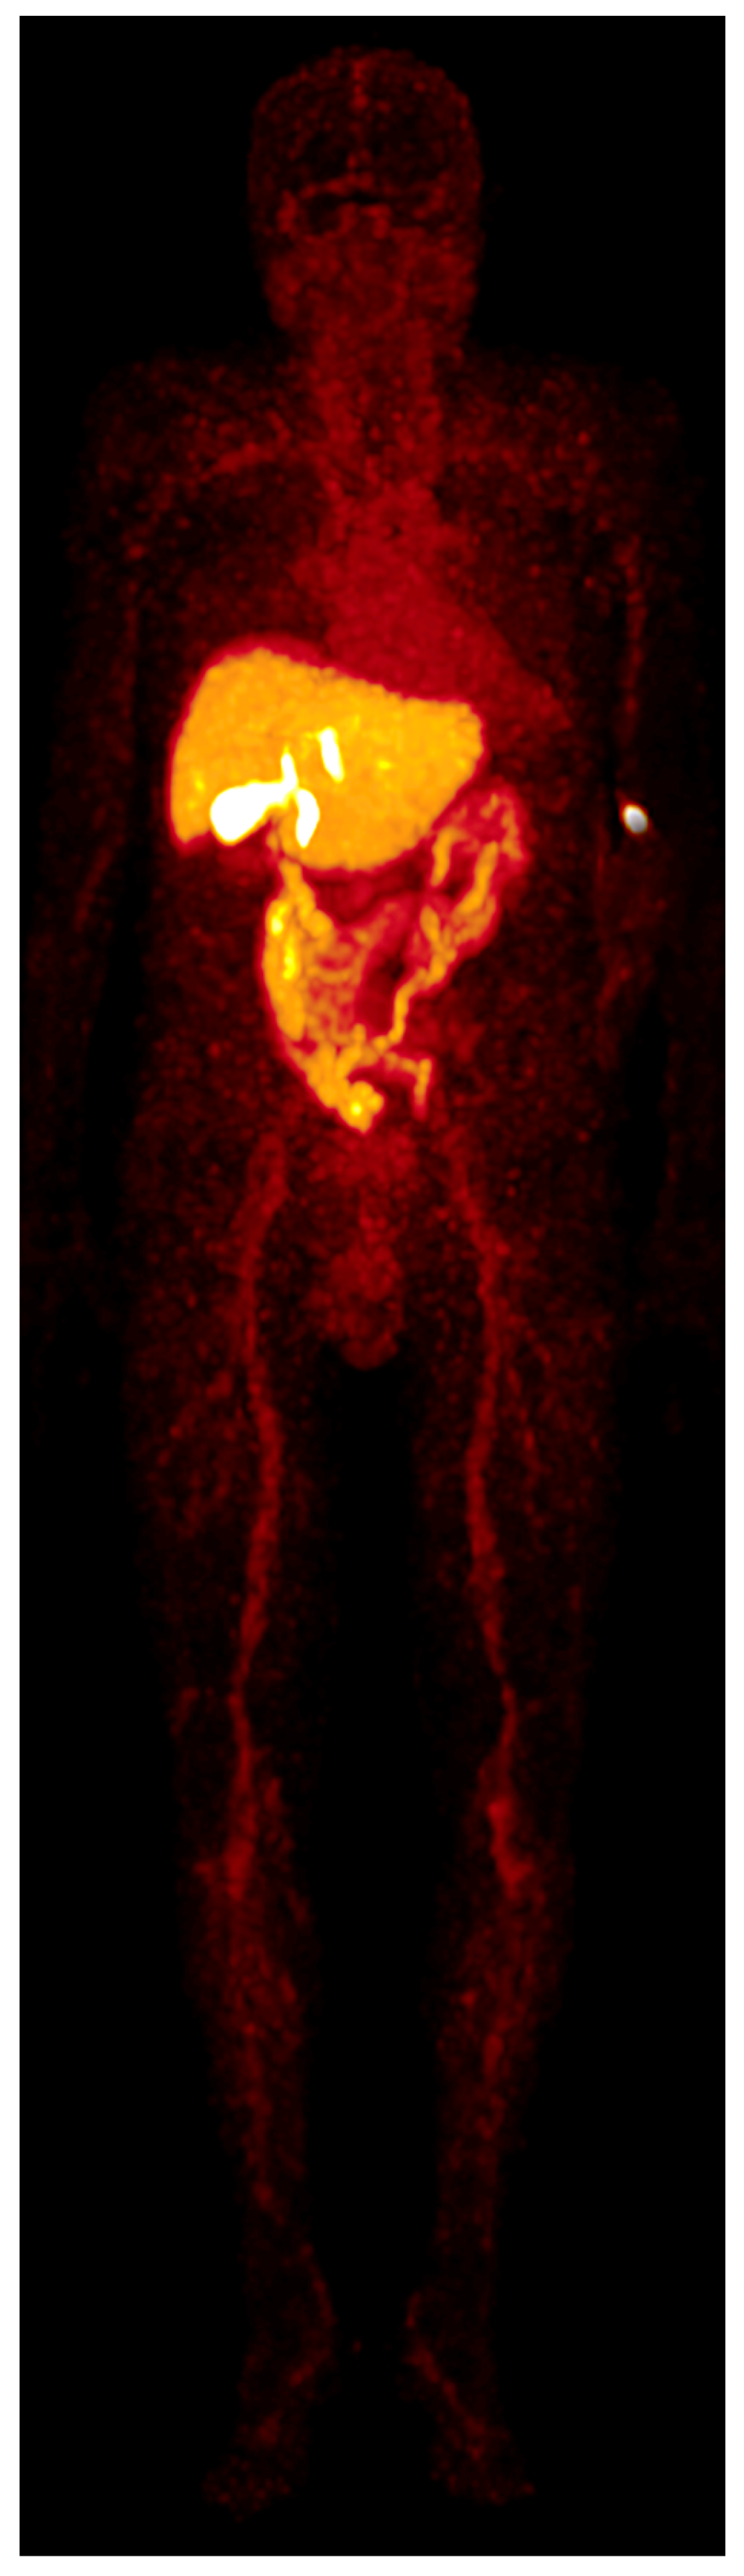

Figure 5. Whole-body MIP was acquired 60 min after the radiotracer injection, patient A. No relevant tracer uptake is seen in the bones, brain, or kidneys. Injection site at the left arm.

Two patients (both male; aged 72 and 82 years) underwent [68Ga]Ga-BP-IDA-PET/CT examinations. Activities of 144 MBq and 166 MBq [68Ga]Ga-BP-IDA, respectively, were prepared and injected intravenously. No immediate or delayed complications occurred. After intravenous administration, [68Ga]Ga-BP-IDA showed rapid liver tissue accumulation with a maximum of 41.5% of the injected activity (SUVmax 18.2) (Figure 2, Figure 3 and Figure 4). Biliary excretion was evident after 15 min with passage to the common hepatic duct. Tracer accumulation in the gall bladder was initially seen after 18 min, but continued to increase further, up to a SUVmax of 48.3 after 60 min. After 30 min, the transition to the duodenum and jejunum had already begun (Figure 4). Liver tissue uptake started to decrease slowly after 18 min, but still represented 37.4% of the administered activity after 60 min. No relevant uptake was seen in the spleen or the skeletal system. The radiotracer showed no significant urinary excretion (maximum kidney uptake of 1.7% of the administered activity after 18 min) (Figure 5). [68Ga]Ga-BP-IDA uptake in the HCC was considerably lower than in non-cancerous tissue of the liver but higher than the background activity (Table 2, Figure 3).

Measurements showed no relevant urinary excretion of [68Ga]Ga-BP-IDA. As little as 0.5% of the injected activity was detected in the urinary bladder after 60 min, similar to [99mTc]Tc-mebrofenin excretion (0.57%). For other IDA agents, higher urinary excretion rates ranging from 5–18% were demonstrated [1]. Due to the high lipophilic character of the gallium complex, urinary excretion of [68Ga]Ga-BP-IDA seems to be unaffected by high bilirubin serum levels, since the competitive action of bilirubin typically decreases biliary excretion and increases renal excretion of 99mTc-IDA agents [4,13].